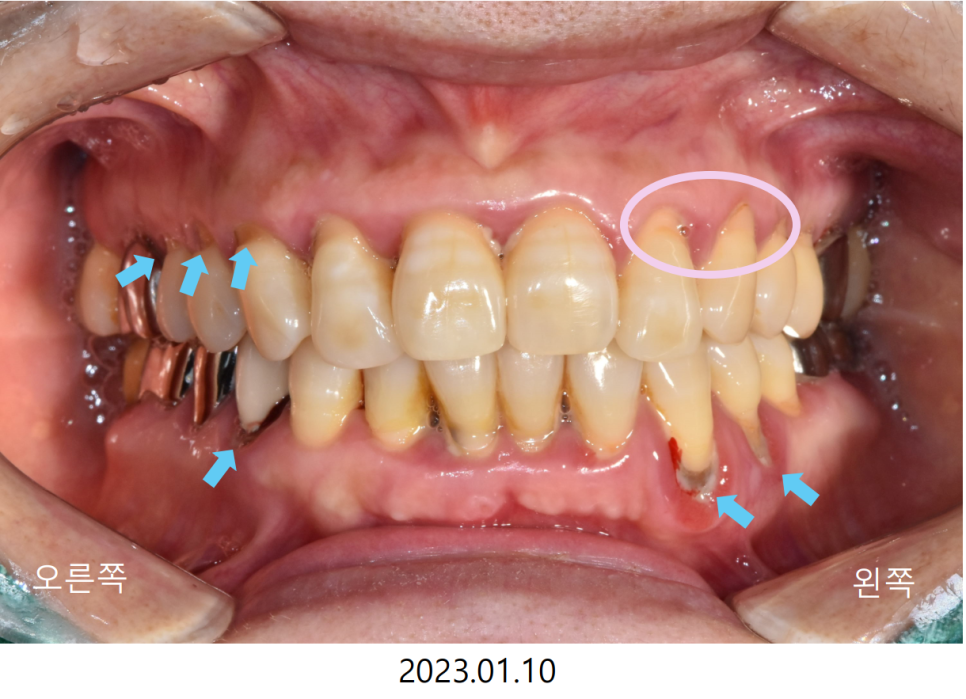

정면사진과 좌우 측면사진에서 치아 목 부위가

V자로 깨져 나간 것이 확인됩니다.

이전에 깨져 나간 목 부위를 치료한 곳도 있지만

왼쪽 불편감이 있는 치아들이

제대로 기능을 못하는 동안

오른쪽을 무리하게 사용하여

다른 치아들이 고생한 것을 알 수 있습니다.

통증이 있는 왼쪽의 경우

잇몸의 발적도 굉장히 심한 상태입니다.

또한 치아를 감싸고 있는 잇몸들이

전체적으로 많이 부어 있어

식사를 하실 때 먹먹한 통증을 매번 느끼셨다고합니다.